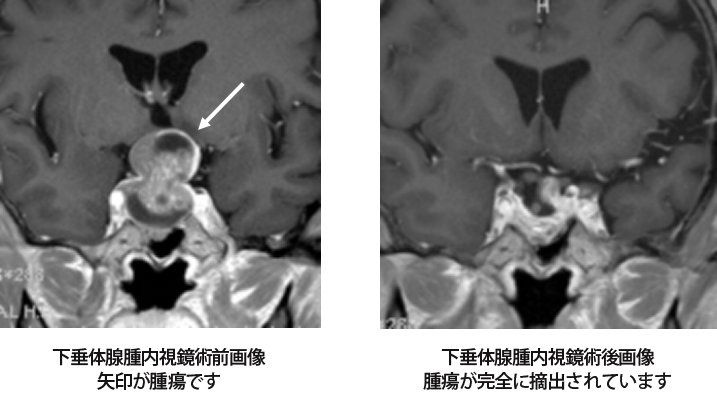

「神経内視鏡手術 技術認定から応用まで」寺本 明定価: ¥ 10000#寺本明 #寺本_明 #本 #自然/医療・薬学・健康ほぼ未使用です。表紙には細かな傷はありますが、状態は綺麗で書き込みなどは確認した限りありません。